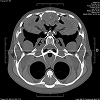

Our 7,000 sq. ft. state-of-the-art laboratory is equipped with advanced diagnostic technology and staffed by highly skilled professionals. An experienced panel of doctors across Pathology, Microbiology, Biochemistry, and Radiology ensures accuracy through expert supervision of every process.